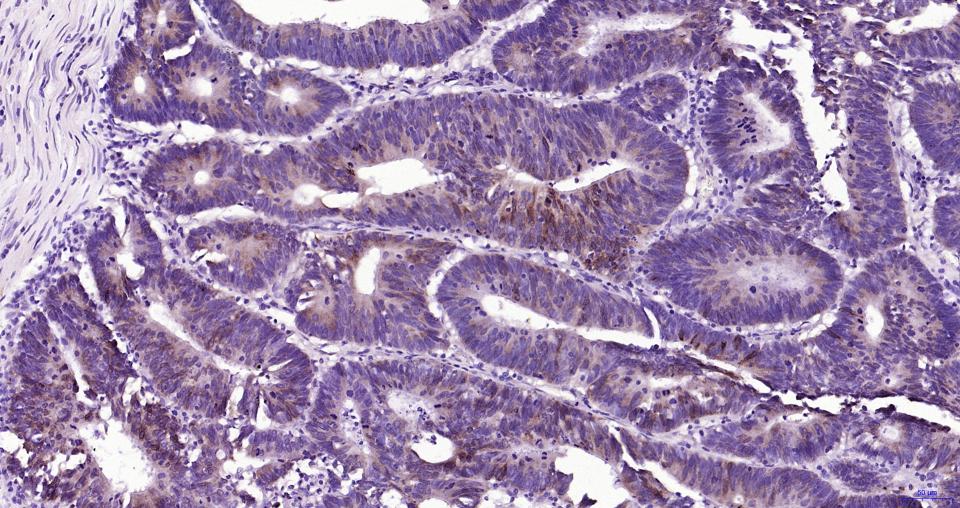

Paraformaldehyde-fixed, paraffin embedded Human Pancreatic Cancer; Antigen retrieval by boiling in sodium citrate buffer (pH6.0) for 15 min; Antibody incubation with MUC5AC Monoclonal Antibody, Unconjugated(bsm-61467R) at 1:200 overnight at 4°C, followed by conjugation to the SP Kit(Rabbit, SP-0023) and DAB (C-0010) staining.